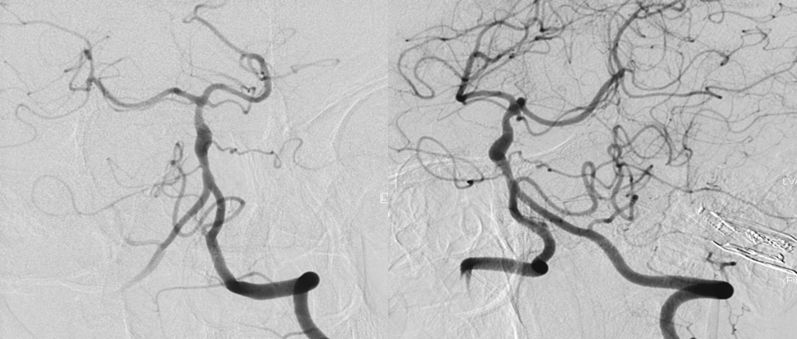

本院DSA:基底动脉巨大夹层动脉瘤,双侧后交通动脉未见明显开放(图6)。

图6

2、头部核磁共振显示:脑干占位性病变,边界较清晰,较大层面大小约35 mmx25 mm。MRA显示:基底动脉夹层动脉瘤。DSA显示,基底动脉巨大夹层动脉瘤,最大长径为:10.8 mm,最大短径为3.2 mm。根据患者症状及影像学诊断,基底动脉巨大夹层动脉瘤进行性增大压迫脑干,不排除脑干水肿可能,亟待手术治疗。

3、因为双侧后交通动脉未见明显开放,为保证脑干血供,手术必须确保载瘤动脉通。动脉瘤累及左侧AICA,基底动脉穿支丰富,位置深在,而且动脉瘤为夹层动脉瘤开颅手术治疗困难,且风险极高。回顾文献及本中心治疗经验,此类动脉瘤血流导向设备疗效较好,经科内讨论后决定运用Tubridge血流导向设备治疗。